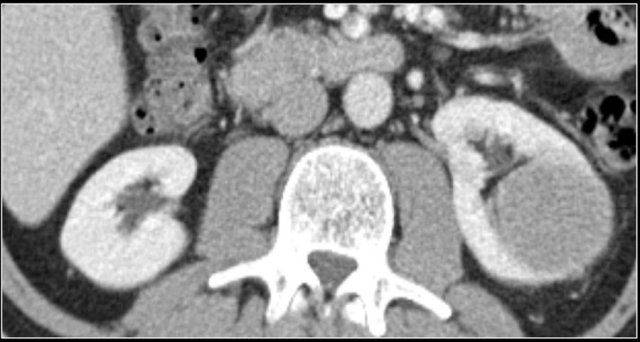

A typical feature of clear cell carcinoma is strong enhancement in the corticomedullary phase.

This can be difficult to assess when the lesion is small and located in the renal cortex, which also enhances strongly.

The nephrogenic phase is therefore the most sensitive phase for the detection of these lesions, as the renal parenchyma enhances homogeneously and more intensely than the tumor (figure).

The corticomedullary phase 25-40 sec post injection is strongly recommended. It helps to differentiate tumor from pseudotumor and to assess enhancement of a lesion.

In this phase however a tumor located in the renal medulla can have the same attenuation as the surrounding parenchyma (figure).

Therefore the nephrogenic phase (±100 sec post injection) is the most important phase for the detection of a tumor.